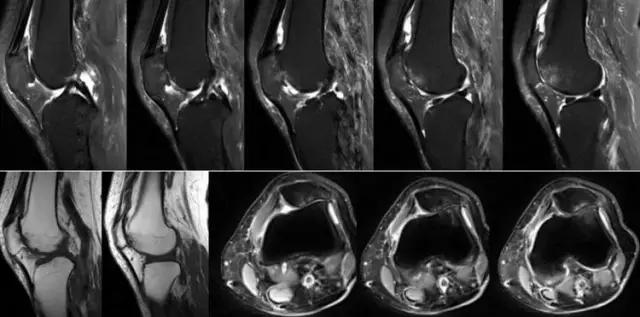

半月板损伤的分度——

Normal:正常的半月板为均匀的低信号。Grade1:半月板内部小灶性的类圆形信号增高影,未达半月 板表面,代表退变性改变。Grade2:半月板内部线形的中等信号增高影,未达半月板表面,代表退变性改变。Grade3:达到半月板关节面的异常信号,可为线形或不规则形,通常代表半月板撕裂。韧带损伤的分级(对所有韧带适用)——Grade1:韧带内损伤,无长度改变。Grade2:韧带内损伤并长度延长。Grade3:完全性韧带撕裂。

地中海贫血与白血病均为血液系统的问题,主要表现在骨髓,疾病的发病机理有别,MRI表现也不相同;我们可能不是很熟悉这些疾病,也能够从MRI发现区别。图1:正常膝关节 图2:地中海贫血 图3:白血病

我们可能都不熟悉T1、T2,怎么办?当我们发现有问题后,利用照片上图像的对比,推测病变的可能也是一种诊断方法。病例:黄XX,女,39岁,左膝关节反复交锁1年。图1:肿物信号与骨信号一样图2:肿物信号与骨信号一样图3:肿物信号与骨信号不一样 肿物应该与骨相关,但不是骨性,推断:膝关节滑膜软骨瘤。手术后得到证实。

膝关节OA是临床常见疾病,不断的磨损会引起一系列的改变,表现在X线照片上会出现以下的四大特征。

利用发病机理——

膝关节OA的MRI表现除了以上 X线的四大特征外,还能清晰的显示出滑膜、韧带、半月板、软骨等改变,这正是MRI的优势所在。